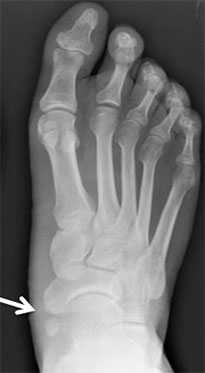

При первом вашем визите в клинику вам будет выполнена рентгенография стоп. Она поможет подтвердить диагноз, оценить тяжесть деформации и при необходимости спланировать хирургическое вмешательство.

Добавочная ладьевидная кость классифицируется в соответствии с рентгенологическими ее особенностями:

- Сесамовидная косточка в толще сухожилия задней большеберцовой мышцы в области его прикрепления к ладьевидной кости

- Добавочная ладьевидная кость, сочленяющаяся синхондрозом с ладьевидной костью

- Костный выступ ладьевидной кости

Рентгенограмма стопы при 1 типе добавочной ладьевидной кости

Рентгенограммы стоп: 3 тип добавочной ладьевидной кости